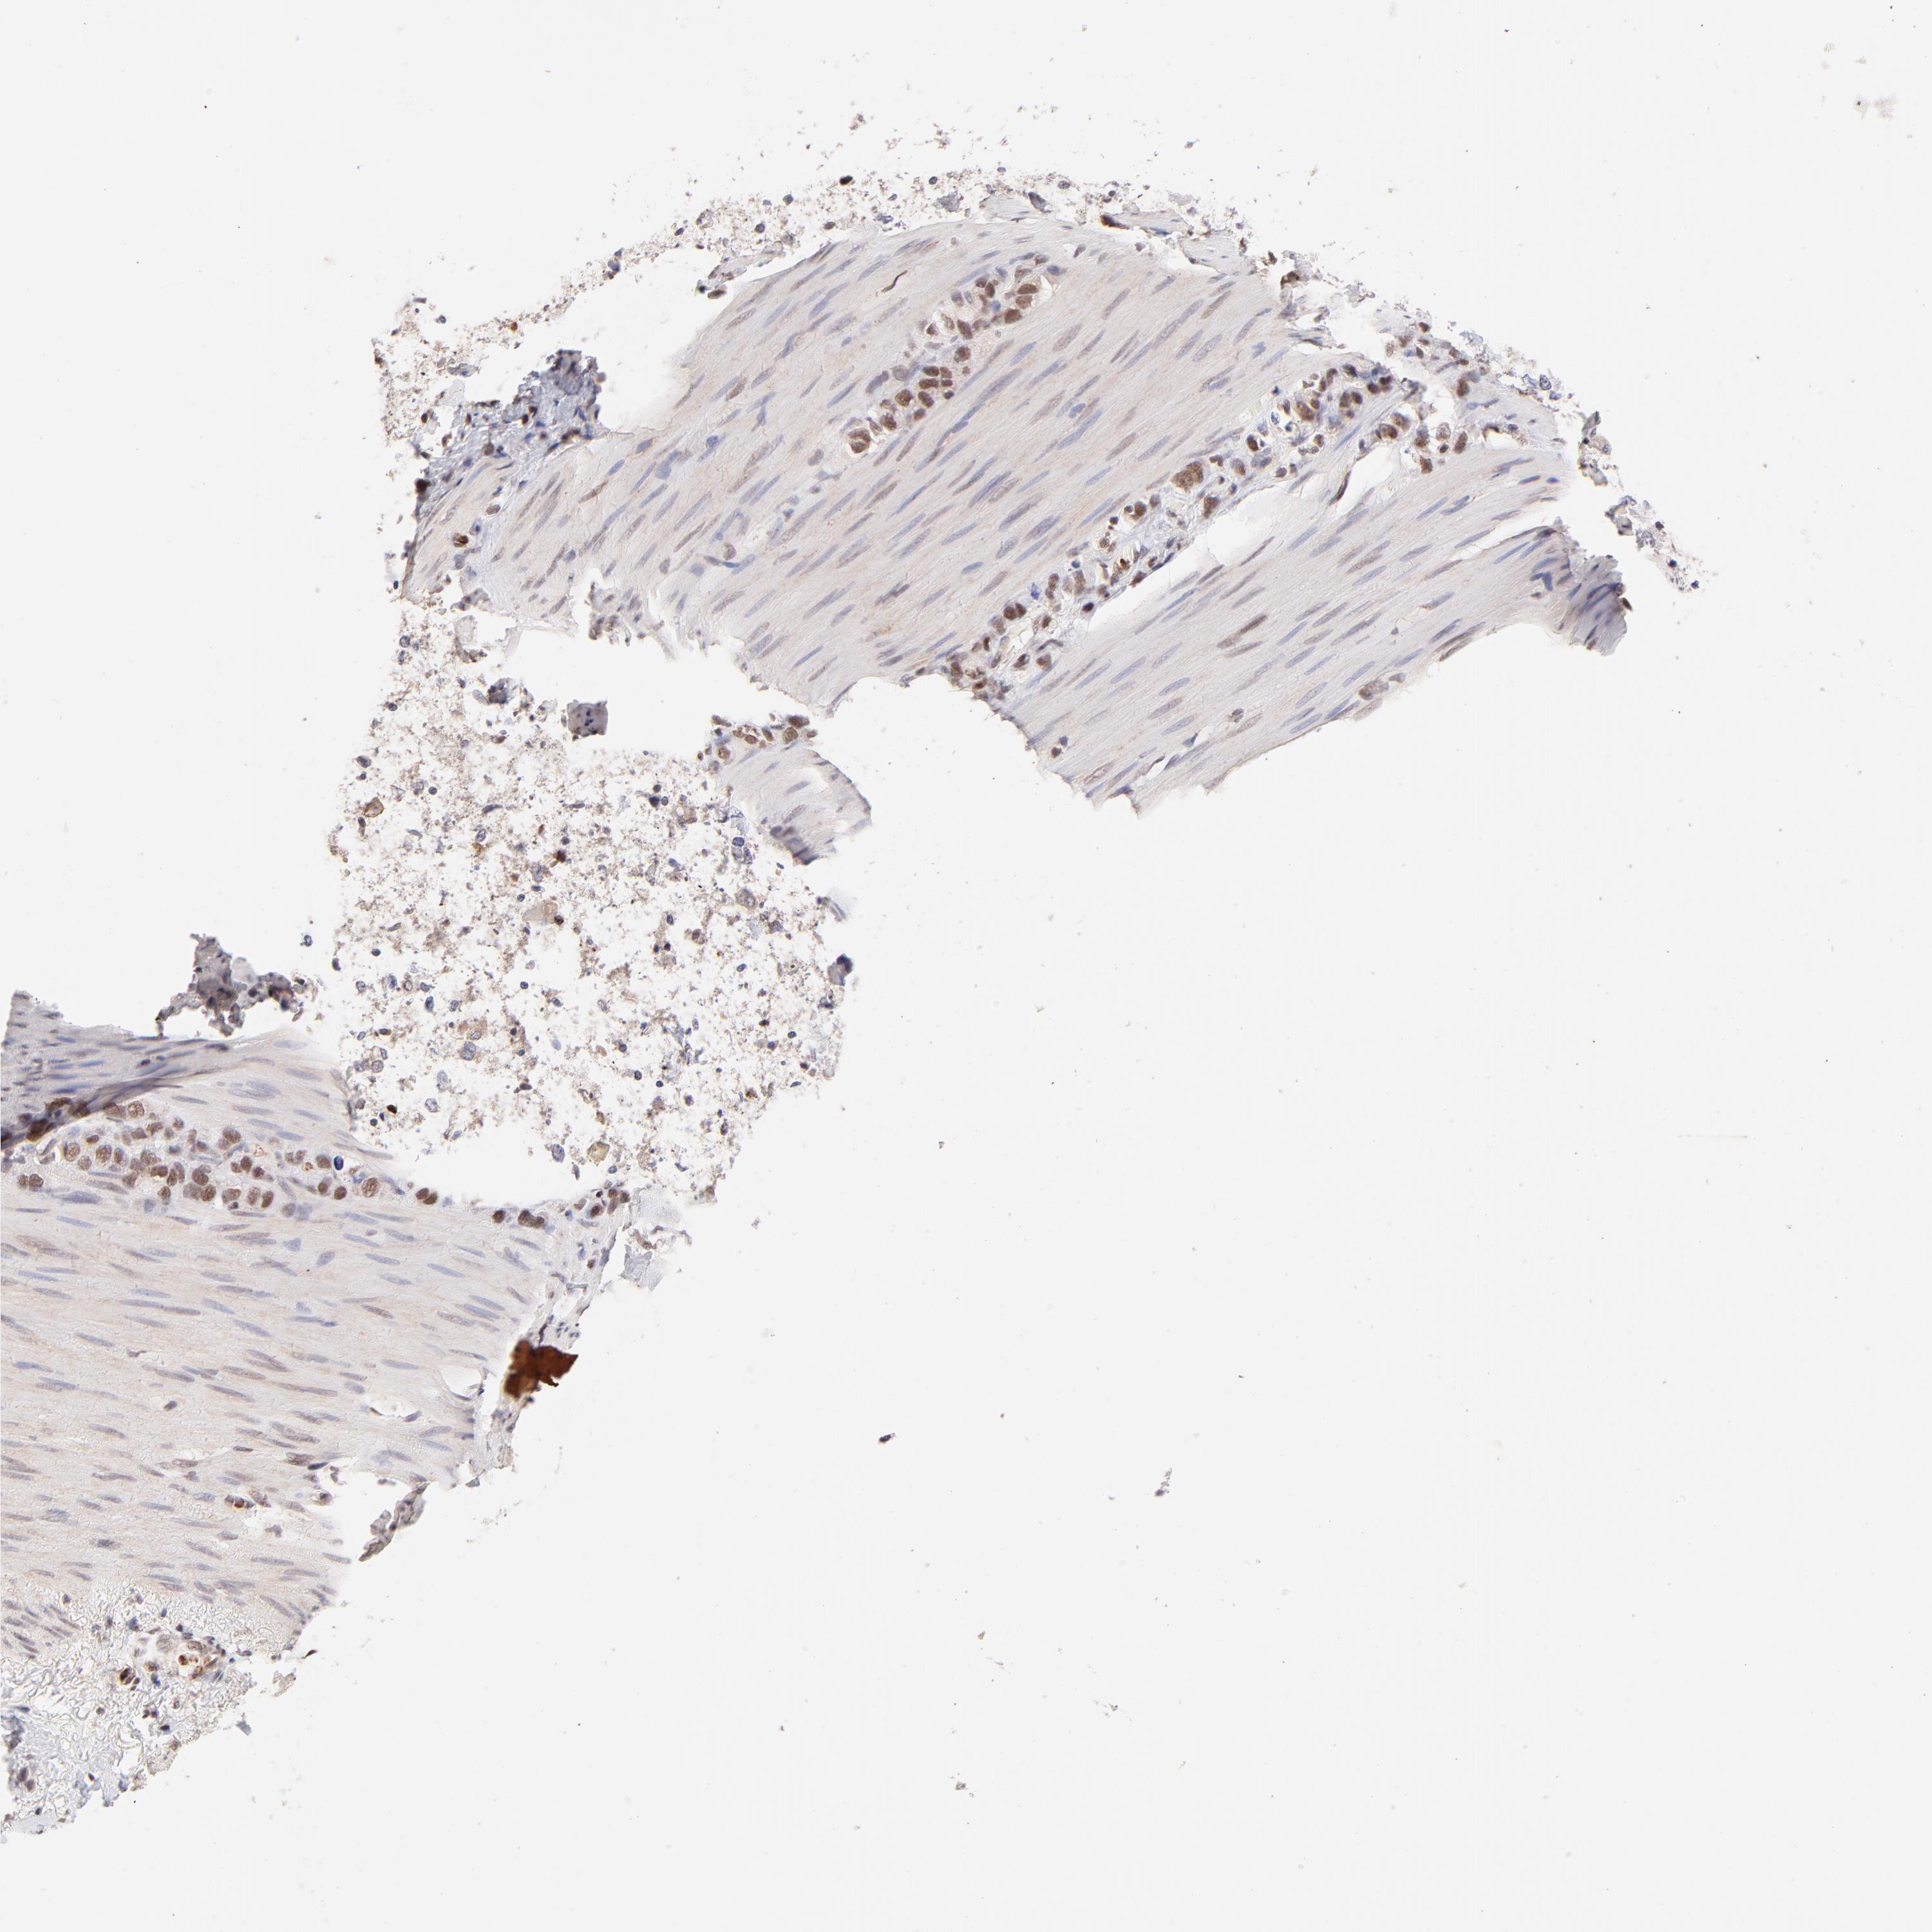

STOMACH CANCER - Protein expressioni

A mouse-over function shows sample information and annotation data. Click on an image to view it in a full screen mode. Samples can be filtered based on level of antibody staining by selecting one or several of the following categories: high, medium, low and not detected. The assay and annotation is described here.

Note that samples used for immunohistochemistry by the Human Protein Atlas do not correspond to samples in the TCGA dataset.

Antibody stainingi

Antibody staining in the annotated cell types in the current human tissue is reported as not detected, low, medium, or high, based on conventional immunohistochemistry profiling in selected tissues. This score is based on the combination of the staining intensity and fraction of stained cells.

Each image is clickable and will lead to virtual microscopy that enables deeper exploration of all samples and also displays staining intensity scores, fraction scores and subcellular localization as well as patient and tissue information for each sample.

Antibody HPA003184

Antibody HPA003185

Staining

High

Medium

Low

Not detected

Intensity

Strong

Moderate

Weak

Negative

Quantity

>75%

75%-25%

<25%

None

Location

Nuclear

Cytoplasmic/membranous

Cytoplasmic/membranous,nuclear

Adenocarcinoma, NOS

Adenocarcinoma, High grade